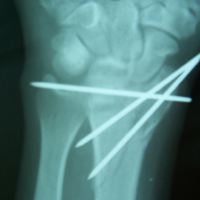

Case:4 Comminuted Intra – Articular Lower End Fracture Radius

A patient, aged 46 years following vehicular accident came with swollen painful wrist & hand. He had been diagnosed to have closed comminuted fracture lower end of right Radius. He was treated operatively with closed reduction & ‘K’ wiring under regional Anaesthesia.

Pre-Op

Pre-op Lateral

Post-op AP

One and Half Months Follow-Up